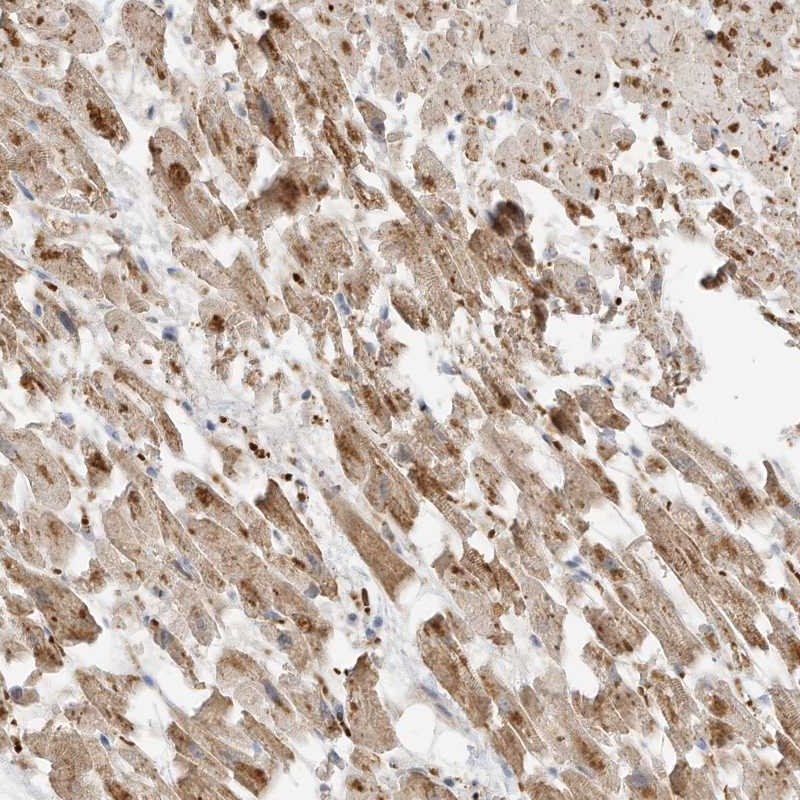

Immunohistochemical staining of human heart muscle shows moderate cytoplasmic positivity in myocytes.